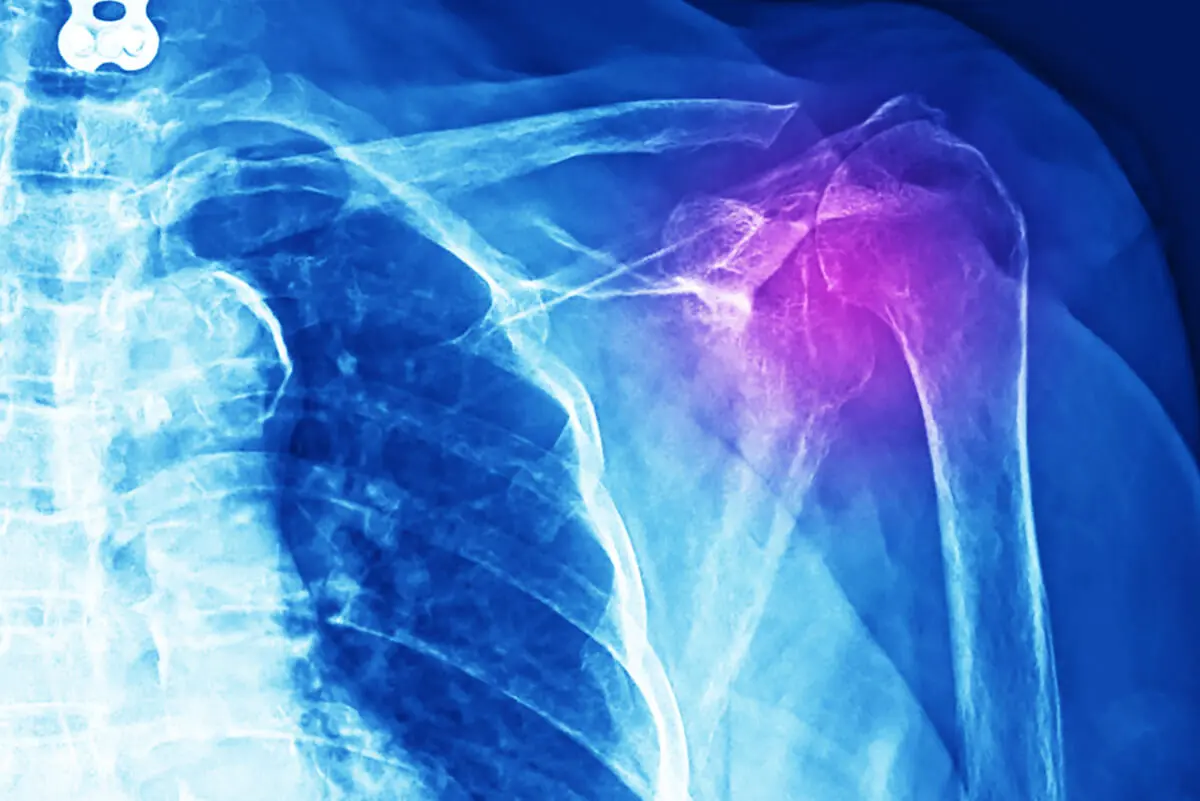

Por otra parte, en el diagnóstico de esta lesión se realizan diversas pruebas, las que incluyen radiografía, ecografía y resonancias. Incluso tomografía axial computarizada (TAC). Además, se hace reconocimiento médico y estudio detallado de la historia clínica del paciente.